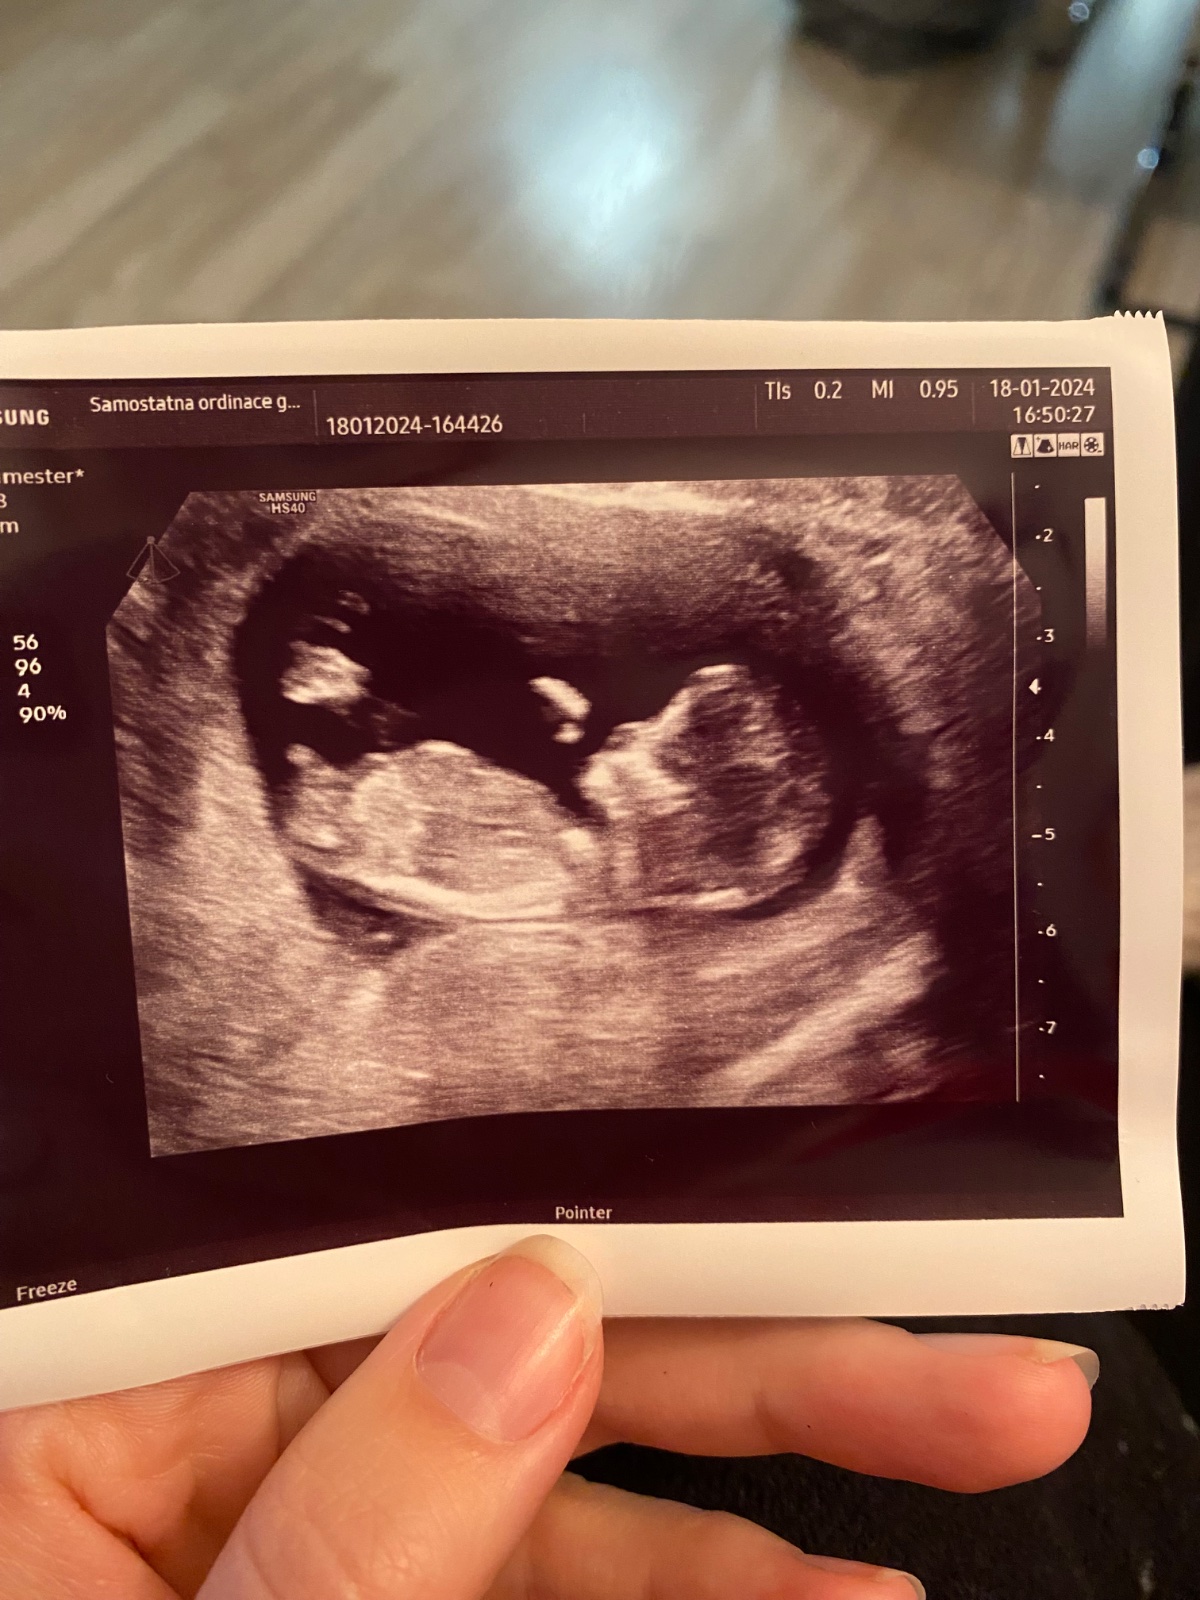

dokázal byste z přiložené fotky odhadnout pohlaví dítěte?

posuzovat pohlaví z jednoho snímku a v prvním trimestru má své velké limitace a vždy je to jen hrubý odhad a dojem. Doporučuji vyčkat na ultrazvuk ve 20. týdnu, tam to bývá již jednoznačné. 🙂